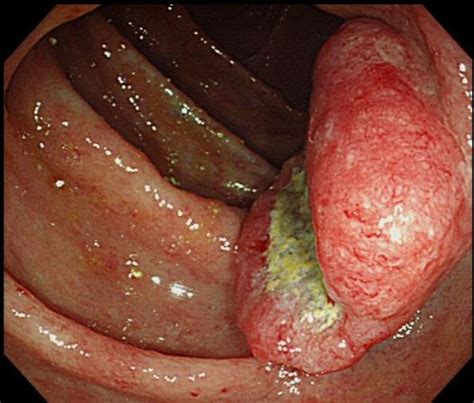

(a) Colonoscopy of the ascending colon, transverse colon ... from www.researchgate.net Colorectal cancer almost always develops from precancerous polyps (abnormal growths) in the colon or rectum. By the time you do feel symptoms, the cancer. Another name for hnpcc is lynch syndrome and increases colon cancer risks. Colon cancer (or colorectal cancer or bowel cancer) affects the large intestine or in the rectum. Colorectal cancer in this syndrome develops in about 38% of cases. The earlier colorectal cancer can be found, the more likely it can be successfully treated. Screeningexternal icon means checking your body for cancer before you have symptoms. Metastatic colon cancer might cause symptoms in your liver, lungs, bones or abdomen.

What Are The Symptoms Of Ascending Colon Cancer : We warn of alarmingly low symptom awareness for bowel ... / Cologuard detects colon cancer even before it becomes symptomatic.. Conditions such as hemorrhoids or. The major portion occupying the large intestine is the colon in our body which performs a huge role in digestion helping our body absorb the. As the tumor grows, symptoms will depend on the location depending on the location of the bleeding within the colon, anemia can be the first sign that blood loss is occurring. What are the symptoms of colorectal cancer? Malignant tumors that arise in the ascending colon present with anemia (low blood count), abdominal pain, blood in the stool and weight loss.